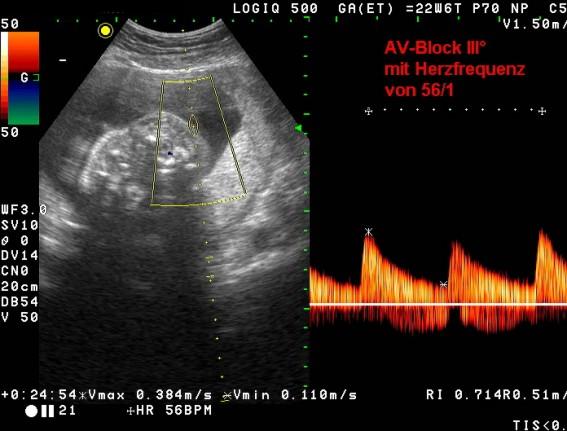

· bei einigen Schwangeren SS-A(Ro)-AK; Störung des Reizleitungssystems des fetalen Herzens - AV-Block III°, davon 50% nach der Geburt therapiebedürftig (Schrittmacher !)

Einige Schwangere mit LE bilden SS-A(Ro)-Antikörper. Diese führen zu einer Störung des Reizleitungssystems des kindlichen Herzens. Infolge dessen kommt es bei 5% der Kinder in der Schwangerschaft zur Ausbildung einer teilweisen Blockade der autonomen Reizübertragung zwischen den Herzvorhöfen und -kammern (AV-Block III°). Davon sind ca. 50% nach der Geburt therapiebedürftig bis hin zur Schrittmacherpflichtigkeit.

AV-Block III. Grades Rippenfellerguss wegen Herzinsuffizienz bei AV-Block III. Grades

Durch die aus dem AV-Block resultierende Herzinsuffizienz kann es vorgeburtlich zum Austritt von Körperflüssigkeit in die Körperhöhlen des Kindes kommen (Nicht-Immunologischer Hydrops Fetalis, NIHF). Die obenstehenden Ultraschallbilder einer Schwangerschaft in der 23. Schwangerschaftswoche (SSW) demonstrieren diesen Sachverhalt.

Es erhebt sich hieraus die Forderung nach Ultraschallkontrollen durch einen erfahrenen Untersucher in der 13./14. SSW (früher Fehlbildungsausschluss), der 21./22. SSW (Organdiagnostik, insbesondere des Herzens) und ab der 26. SSW mindestens zweiwöchentlich (Untersuchung des Herzens und Überprüfung der Versorgung des Kindes durch Blutflussmessungen, der sogenannten Doppleruntersuchung).